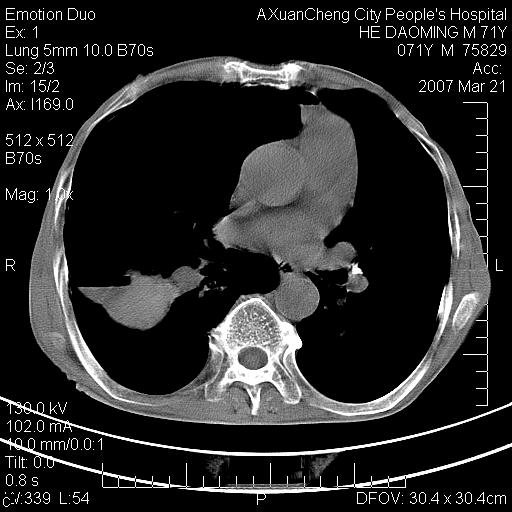

标题: CT7269:[原创] 咳嗽,咳痰,大家讨论右肺病变的部位 [打印本页]

标题: CT7269:[原创] 咳嗽,咳痰,大家讨论右肺病变的部位

1.慢支肺气肿 肺心病 肺大泡;2.叶间裂积液,前胸膜粘连

右侧相当于叶间软组织样密度ct值约50hu,请大家讨论是什么性者病变

考虑:慢性支气管炎合并全小型肺气肿、肺大泡、间质纤维化、感染,右斜裂积液。

考虑慢支,肺气肿,肺大泡,间质纤维化;右侧斜裂液气胸考虑(可能因为肺大泡破裂破入斜裂所致).

考虑病变以右上中肺多发肺大泡为主并感染。请结合临床考虑慢支肺气肿,肺心病。

1双肺慢性支气管炎并全小叶型肺气肿肺大泡2间质性纤维化3右侧斜裂积液

考虑:慢性支气管炎合并右侧全小型肺气肿、肺大泡并感染、双肺间质纤维化,右斜裂积液。

如果患者变化一下体位扫描可分辨液平与斜裂的关系。